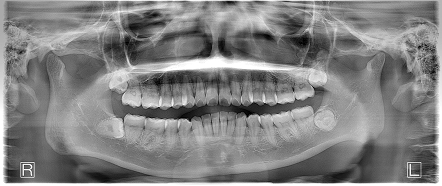

お口の中全体の写真

After

- 1年1か月、来院回数15回

- 上の出っ歯は矯正治療前よりもひっこみ、前歯が全体的に整って綺麗な歯並びとなりました。